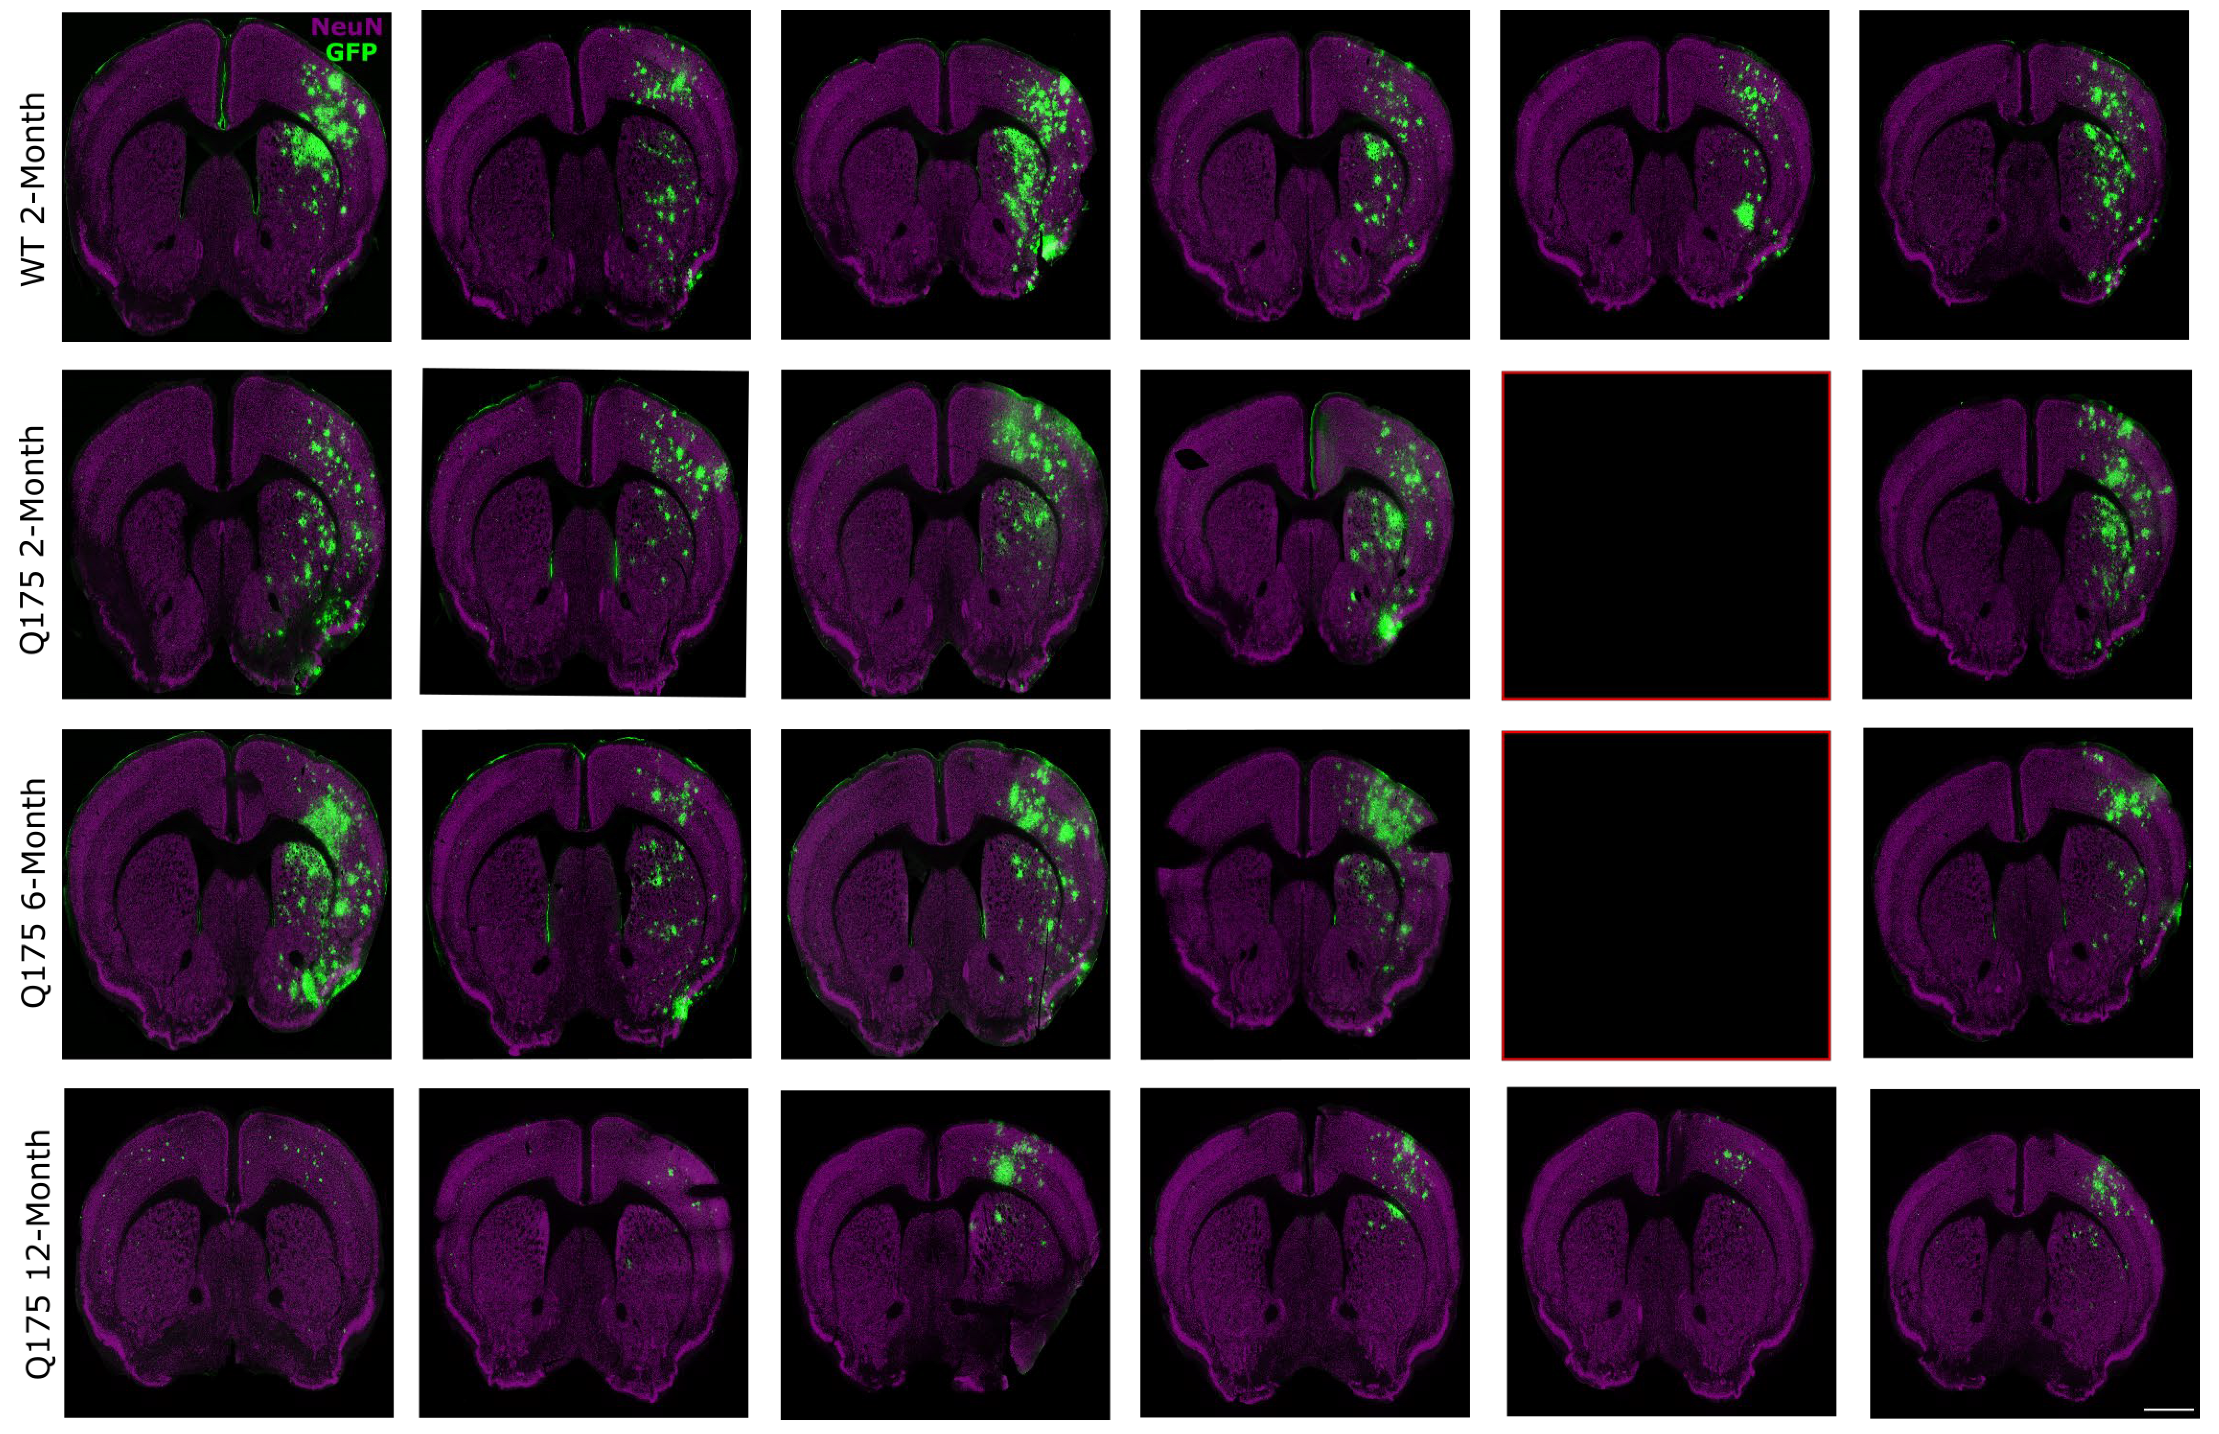

3.2. FUS-Mediated AAV9 Delivery Restricted Transgene Expression to Sonicated Hemisphere

| Group | n | Mouse Strain | Age at Treatment | FUS Target |

|---|---|---|---|---|

| 1. WT 2-month | 6 | C57BL/6J | 2 months | Right caudate putamen |

| 2. zQ175 2-month | 6 * | B6J.zQ175 KI | 2 months | Right caudate putamen |

| 3. zQ175 6-month | 6 † | B6J.zQ175 KI | 6 months | Right caudate putamen |

| 4. zQ175 12-month | 6 | B6J.zQ175 KI | 12 months | Right caudate putamen |